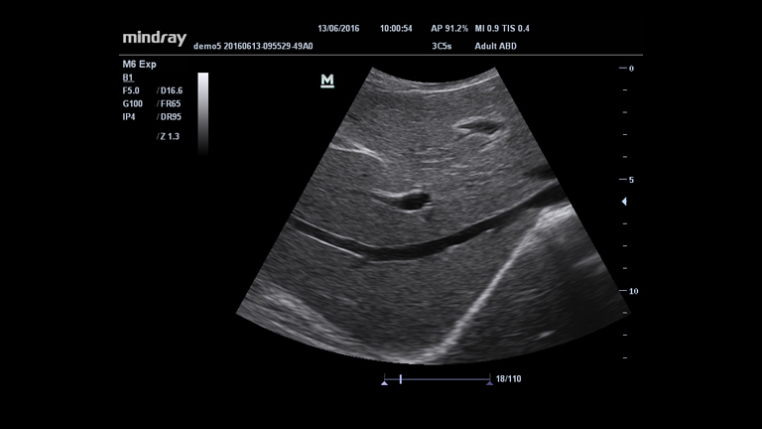

It has been a long, challenging path for clinicians to bring high-level standard diagnosis to the bedside for intensive patient care. Up to now, there has been a limited choice of size and performance of traditional ultrasound systems.With health care within reach in mind, Mindray released the new M6, the ideal balanced of capability and size to realize a confident diagnosis at the bedside.

Maximum 8 times tasking for one transmitted beam, resulting in excellent time resolution and higher frame rate.

Gain improved image quality based on auto structure detection.

- Sharper & Continuous Edges

- Smooth Uniform Tissues

- Cleaner ŌĆśno echo areasŌĆÖ